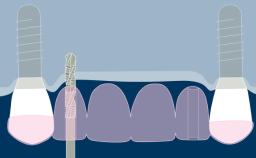

Prosthodontic Planning and Procedures

Implant-Supported Provisional Prosthesis

Learning Module